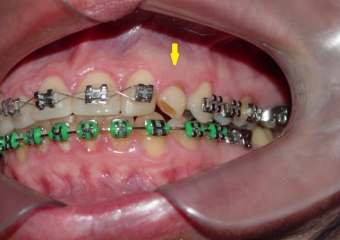

Imagem inicial com presença de canino decíduo